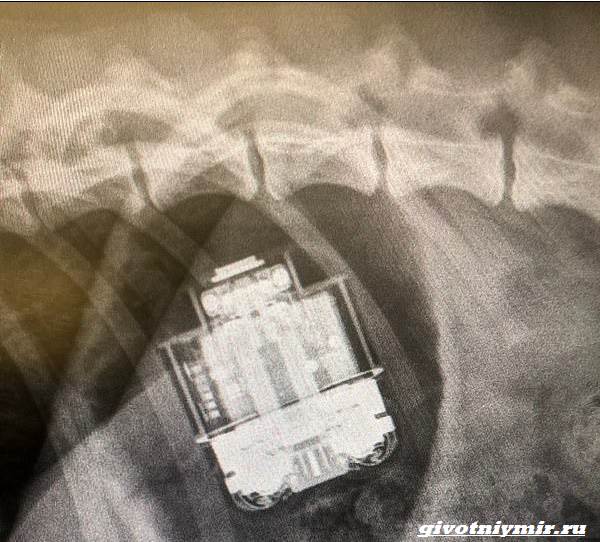

Понимая, что питомцу срочно требуется помощь, девушка обратилась к доктору. Ее встретила главный ветеринар клиники – Сюзанна Жауреги. Она выслушала хозяйку и предложила сделать Джимми рентген, чтобы оценить сложившуюся ситуацию. Увидев небольшую коробочку внутри тела питомца, ветеринар опешила, после чего поняла, что придется оперировать собаку.

«Снимки показали, что AirPods могут повредить пищеварительную систему», — сообщила девушке ветеринар. Она добавила, что если оставить так, как есть, то это может привести к обструкции и гибели животного. Кроме того, содержимое батарейки могло в любой момент просочиться наружу и вызвать тяжелое отравление и летальный исход.